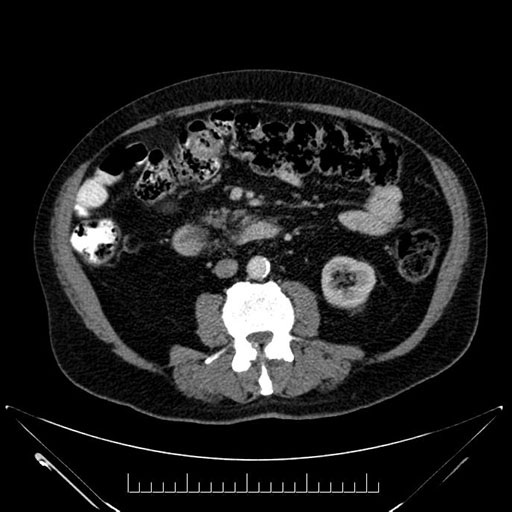

Imaging Analysis

Look through the patient's CT scan to identify any areas of concern for the necessary procedure.

Based on your CT findings, which issue(s) would give reason for "planned slowing down moment(s)" in this case?

Considering a standard Whipple procedure, what step(s) of the operation would you do differently in this case?